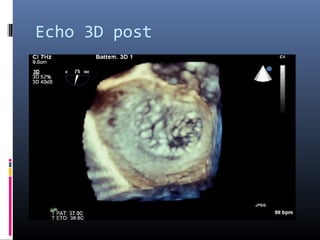

Echo 3D post

La procédure est faite à 100% sous contrôle écho, il faut donc absolument avoir

un appareil d’écho 3D.